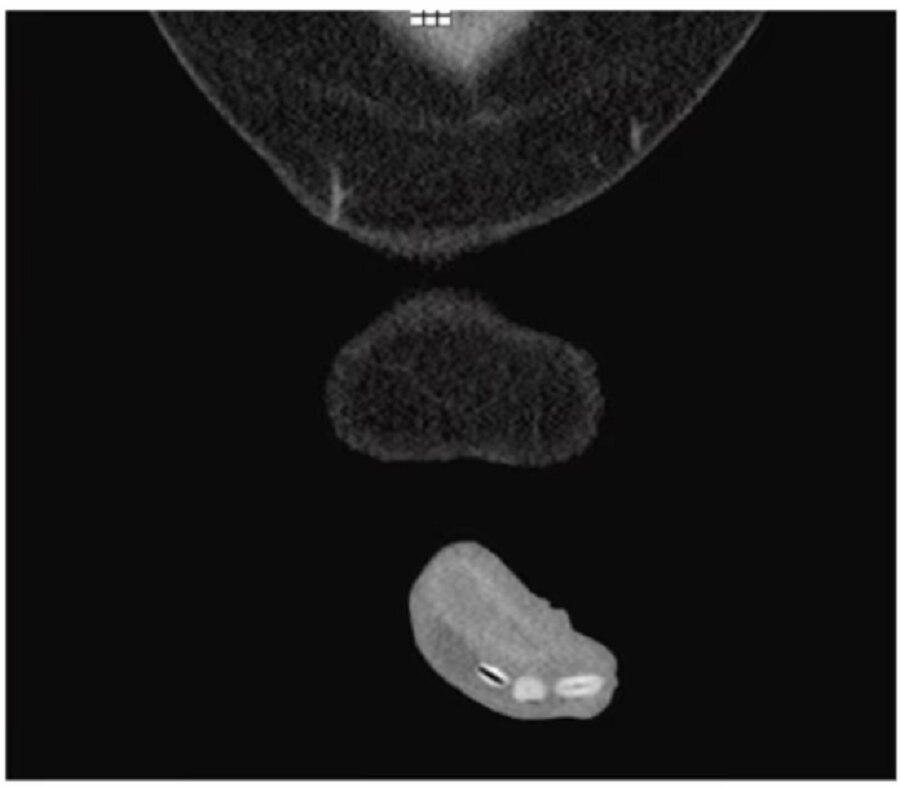

मिशिगन के स्पैरो हॉस्पिटल में इस शख्स को गंभीर हालत में भर्ती कराया गया था. वह दर्द से कराह रहा था और पेशाब भी नहीं कर पा रहा था. जब डॉक्टरों ने चेक किया तो पता चला कि शख्स के प्राइवेट पार्ट में राजमा के 6 दाने फंसे हैं.

यह जानकर डॉक्टर हैरान हो गए थे. हालांकि उस समय डॉक्टर के पास इन सवालों का जवाब खोजने के बजाए, शख्स की जान बचाना जरूरी था. डॉ. मार्गो डेनिस और उनकी टीम ने तत्काल ही शख्स की सर्जरी की और राजमा के 6 दानों को बाहर निकाला जिसके बाद उसकी जान बचाई जा सकी. (प्रतीकात्मक फोटो/Getty images)

डॉ. मार्गो डेनिस ने बताया कि पेशाब नली में राजमा के दाने फंसे हुए थे. हालांकि शख्स ने इन्हें घर पर भी निकालने का प्रयास किया था, लेकिन वह सफल नहीं हुआ. (प्रतीकात्मक फोटो/Getty images)